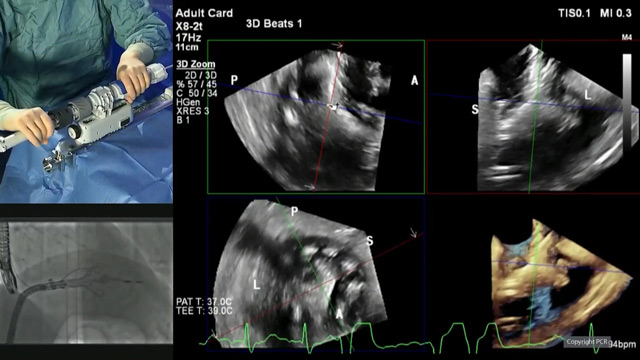

TAVI: when calcifications are the major issues

16 May 2024 – From EuroPCR 2024

This session explores various challenging TAVI cases where severe aortic valve calcification was the main obstacle. Presenters share their experiences and strategies in overcoming these complex anatomical issues, including the use of techniques like the buddy balloon technique, snare technique, and innovative approaches to cross the...

TAVI updates: expanding indications

14 May 2024 – From EuroPCR 2024

This session presents the latest updates and evidence on the expanding indications for transcatheter aortic valve implantation (TAVI). It covers topics such as the impact of unfavorable aortic valve anatomy on TAVI outcomes, sex-specific differences in cardiac damage in aortic stenosis patients undergoing TAVI, the use...

Coronary issues before, during and after TAVI

This session presents a series of challenging clinical cases highlighting the complex interplay between coronary artery disease and transcatheter aortic valve implantation (TAVI). Attendees will witness real-world scenarios, including high-risk PCI with concomitant severe aortic stenosis, the management of degenerated aortic bioprostheses with the risk of...